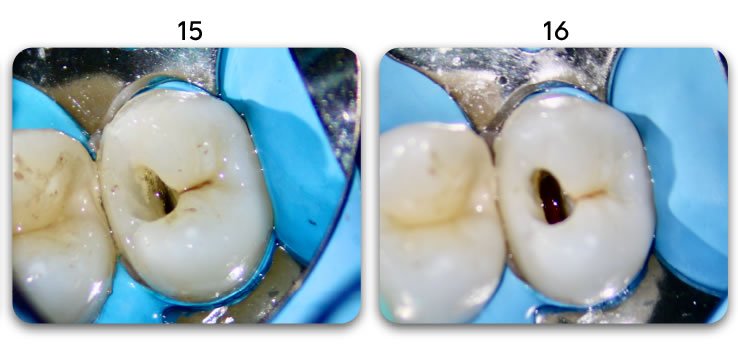

Biolight® DRILL-FREE posts are available in bundles of 4, 6, 9 and 12 strands. The post size is selected based on the width of the canal at the coronal area. Depending upon the canal width at the apical stop, a certain number of strands must be pushed to the stop. Both of the measurements are made with the assistance of a radiograph and the template that is included in the TRAINING KIT.

It is important to follow the steps in the instructional video. There is a procedure that will ensure predictable, bubble-free results (see 1:57 in the video).

As, change is sometimes stressful, we created a Biolight® DRILL-FREE TRAINING KIT that will allow you to place 3 posts on the provided model, prior to doing real cases. You will quickly realize that the procedure is fast and easy. There are also videos, pictures, documentation, and specialised technical support team to help you with any requests you have.